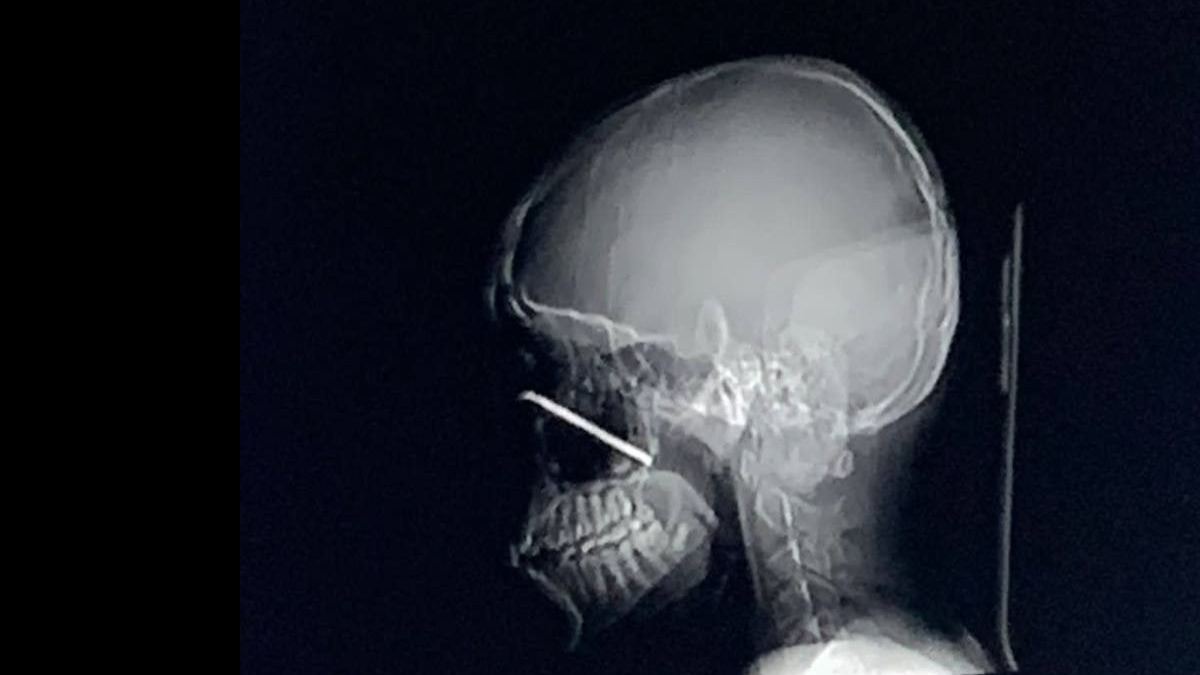

Фото: Пресс-служба Министерства здравоохранения Московской области

Коллектив офтальмологического отделения Московского областного научно-исследовательского клинического института (МОНИКИ) имени Владимирского спасли 12-летнего подростка, вытащив из его глаза металлический прут. Об этом рассказали в пресс-службе министерства здравоохранения Московской области в понедельник, 1 сентября.

Там пояснили, что во время игры в футбол от ворот из-за удара мяча отлетел металлический прут длиной шесть сантиметров, который поразил глаз юноши. Штырь прошел через нижнюю стенку орбиты и оказался за задней стенкой верхнечелюстной пазухи.

— Инородное тело было извлечено, после чего мы ушили рану. Никакого дальнейшего оперативного лечения пациенту не потребуется, но, конечно, он продолжит наблюдаться у нас, — сообщает пресс-служба, ссылаясь на врача-офтальмолога МОНИКИ имени Владимирского Ирину Тарабанько.

В настоящий момент пациент продолжает находиться под присмотром врачей. Зрение подростка удалось сохранить.